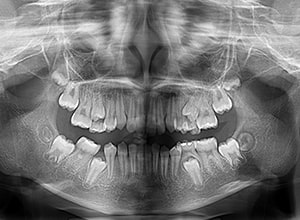

| パノラマ所見 | 右下5は右下6近心傾斜により萌出部位不足が認められた。上下顎8歯胚が確認できた。 |

| 批評・予后 | 右下5及び7の萌出前に右下6を整直させることによって、右下5の自然萌出が可能となり正常咬合への咬合誘導が行えたと思う。 |